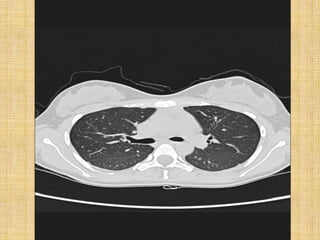

   FULL INSPIRATION

   BREATH HOLD

   EXPIRATORY SCAN WHENEVER INDICATED

   SUPINE AND PRONE IF INDICATED